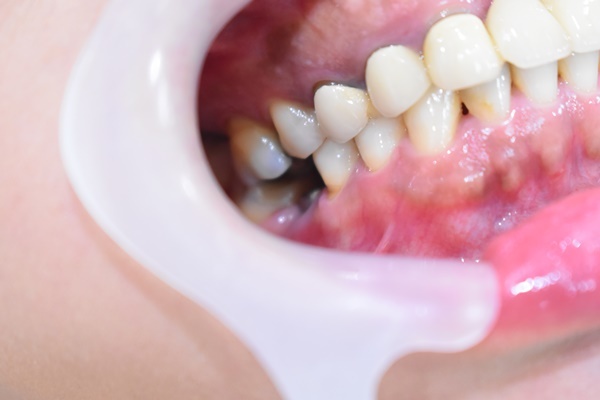

臼齒植牙方式採微創植牙

微創植牙跟傳統人工植牙方式不太一樣

沒有那種血淋淋牙肉切開的疼痛感

手術過程更是比想像中還要來得快速

當晚到診所醫師會先在診療檯做口腔清潔

先將植牙位置鄰近牙齒都洗過一遍

主要是植體種下去後會有傷口

有傷口再就不方便刷牙及吃飯